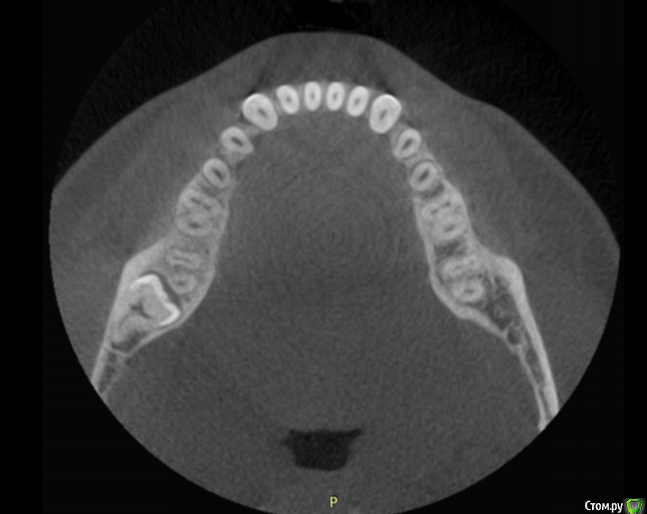

Начинающий хирург. Второй раз сталкиваюсь с такой вот 8ой (48), горизонтально и язычно лежащей. В первый раз удалял по протоколу, описанному Асанами и Касазаки в их учебнике "Квалифицированное удаление третьих моляров."

Хотел бы поинтересоваться у вас, как бы удалили вы?

Если не сложно, распишите поподробней, пожалуйста. Начиная от дизайна разреза, заканчивая ушиванием. Заранее спасибо всем!

Мое мнение: создать хороший доступ и визуальный контакт, аккуратно распилить его по шейке ( обратить внимание на прилегание н/л нерва) разделить и извлечь по частям!